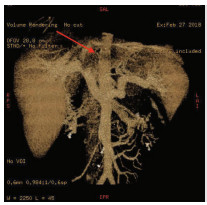

Multidisciplinary treatment of hepatocellular carcinoma with tumor thrombosis in the left portal vein: A case report

Jihong YANG, Guoxiang CHEN, Mo ZHOU, Jisen ZHAO, Yuan WANG, Yuanlong ZHOU

2021, 37(3): 666-679. DOI: 10.3969/j.issn.1001-5256.2021.03.031

Abstract(1185) HTML (567) PDF (3239KB)(69)

Abstract: